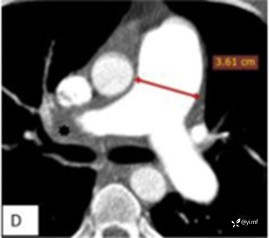

患者年轻男性,因气短2年入院。排除常见的冠心病、肺脏疾病后,结合患者既往肺栓塞病史、超声提示肺动脉压力升高且右心功能不全,自然容易想到「慢性血栓栓塞性肺动脉高压(CTEPH)这一疾病。最后通过Swan-Ganz漂浮导管检查及肺动脉造影(图2),明确CTEPH诊断。

图2 CT肺动脉造影显示右肺动脉有残余慢性血栓,主肺动脉扩张